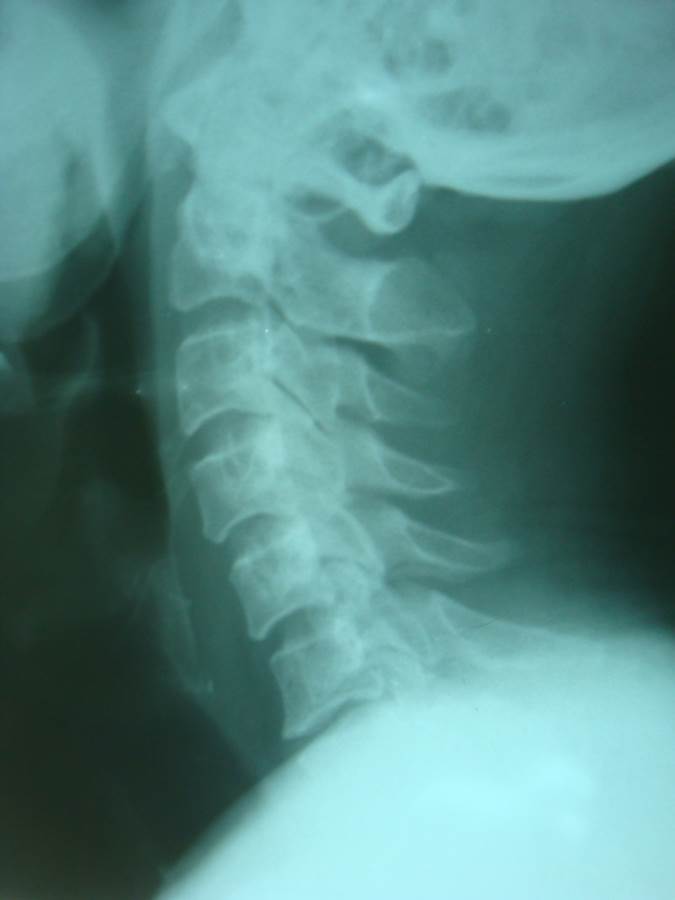

Pre-op xray

Cervical Disc Replacement